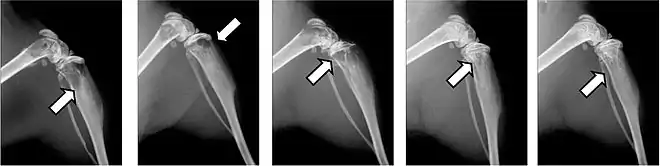

- Vues de fractures pathologiques

Fracture pathologique de l'humérus sur une métastase de carcinome du rein

Fracture pathologique du bras gauche sur une métastase osseuse de cancer du sein

Scintigraphie corps entier avec 99mTc-HDP de la patiente avec une fracture du bras due à une métastase du cancer du sein